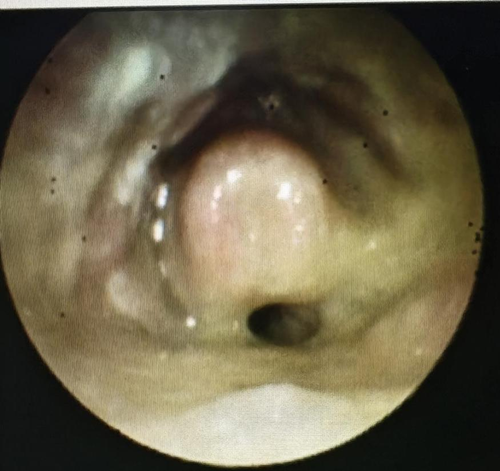

正常舌根-下咽-喉内镜检查图